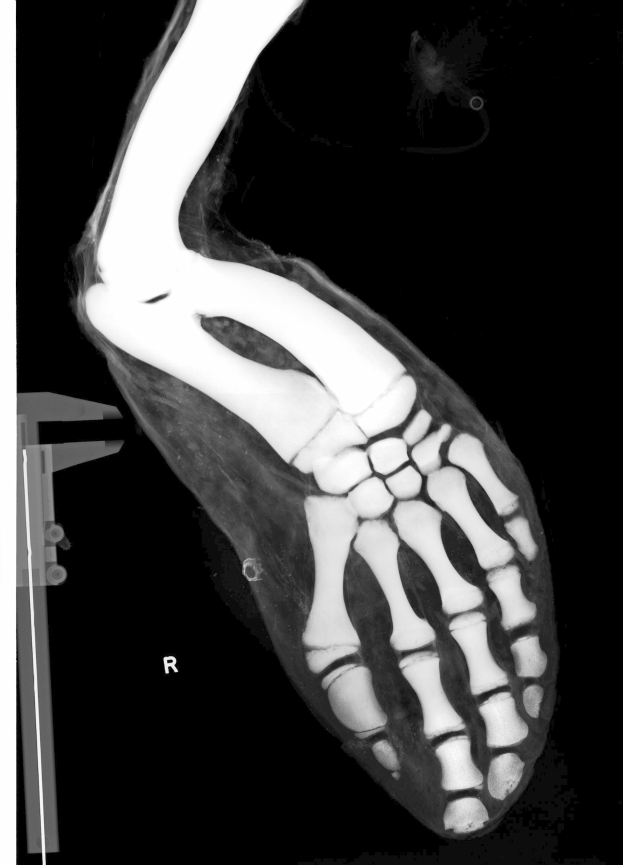

Der 20-jährige Mittelfeldspieler des FC Schalke 04, Mika Khadr, wird nach einer schweren Fußverletzung die gesamte restliche Saison verpassen. Der junge Deutsche zog sich am Sonntag im Spiel einen Knöchelbruch zu und wurde bereits operiert. Sein Ausfall kommt sowohl für den Spieler als auch für die langfristigen Pläne des Vereins zum falschen Zeitpunkt.